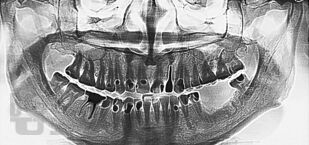

В пособии представлены современные методы ортопедического лечения частичной потери зубов мостовидными протезами. Подробно изложена хирургическая подготовка альвеолярного отростка и альвеолярной части челюстей перед протезированием.